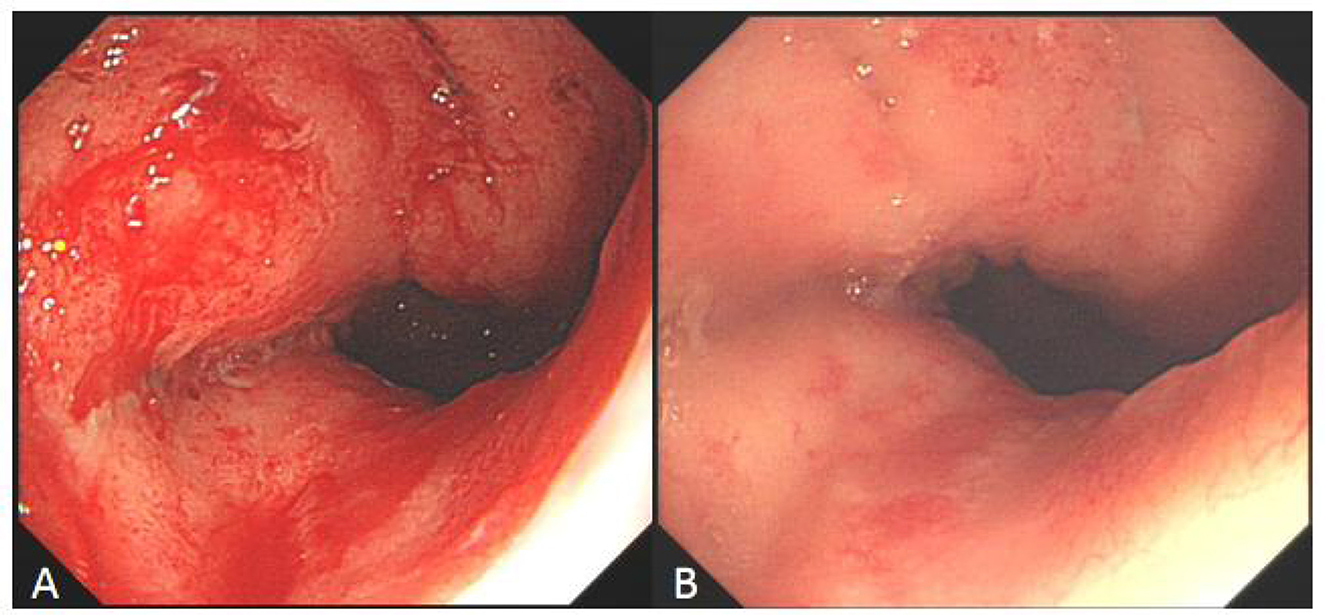

Some cases of hyperbaric oxygen therapy for refractory peptic ulcer disease (Figures 46).

Two endoscopic images labeled A and B show areas of the gastrointestinal tract. Image A displays an inflamed, red mucosal surface with signs of irritation. Image B shows a less inflamed appearance with lighter coloration and fewer visible lesions.

Figure 6. Comparison of refractory ulcer after radiotherapy at esophagogastric anastomosis before and after treatment. (A) Esophagogastric anastomosis showed intractable ulceration and bleeding after radiotherapy. (B) After 2 weeks of hyperbaric oxygen treatment, the ulcer lesions healed markedly and the bleeding stopped.